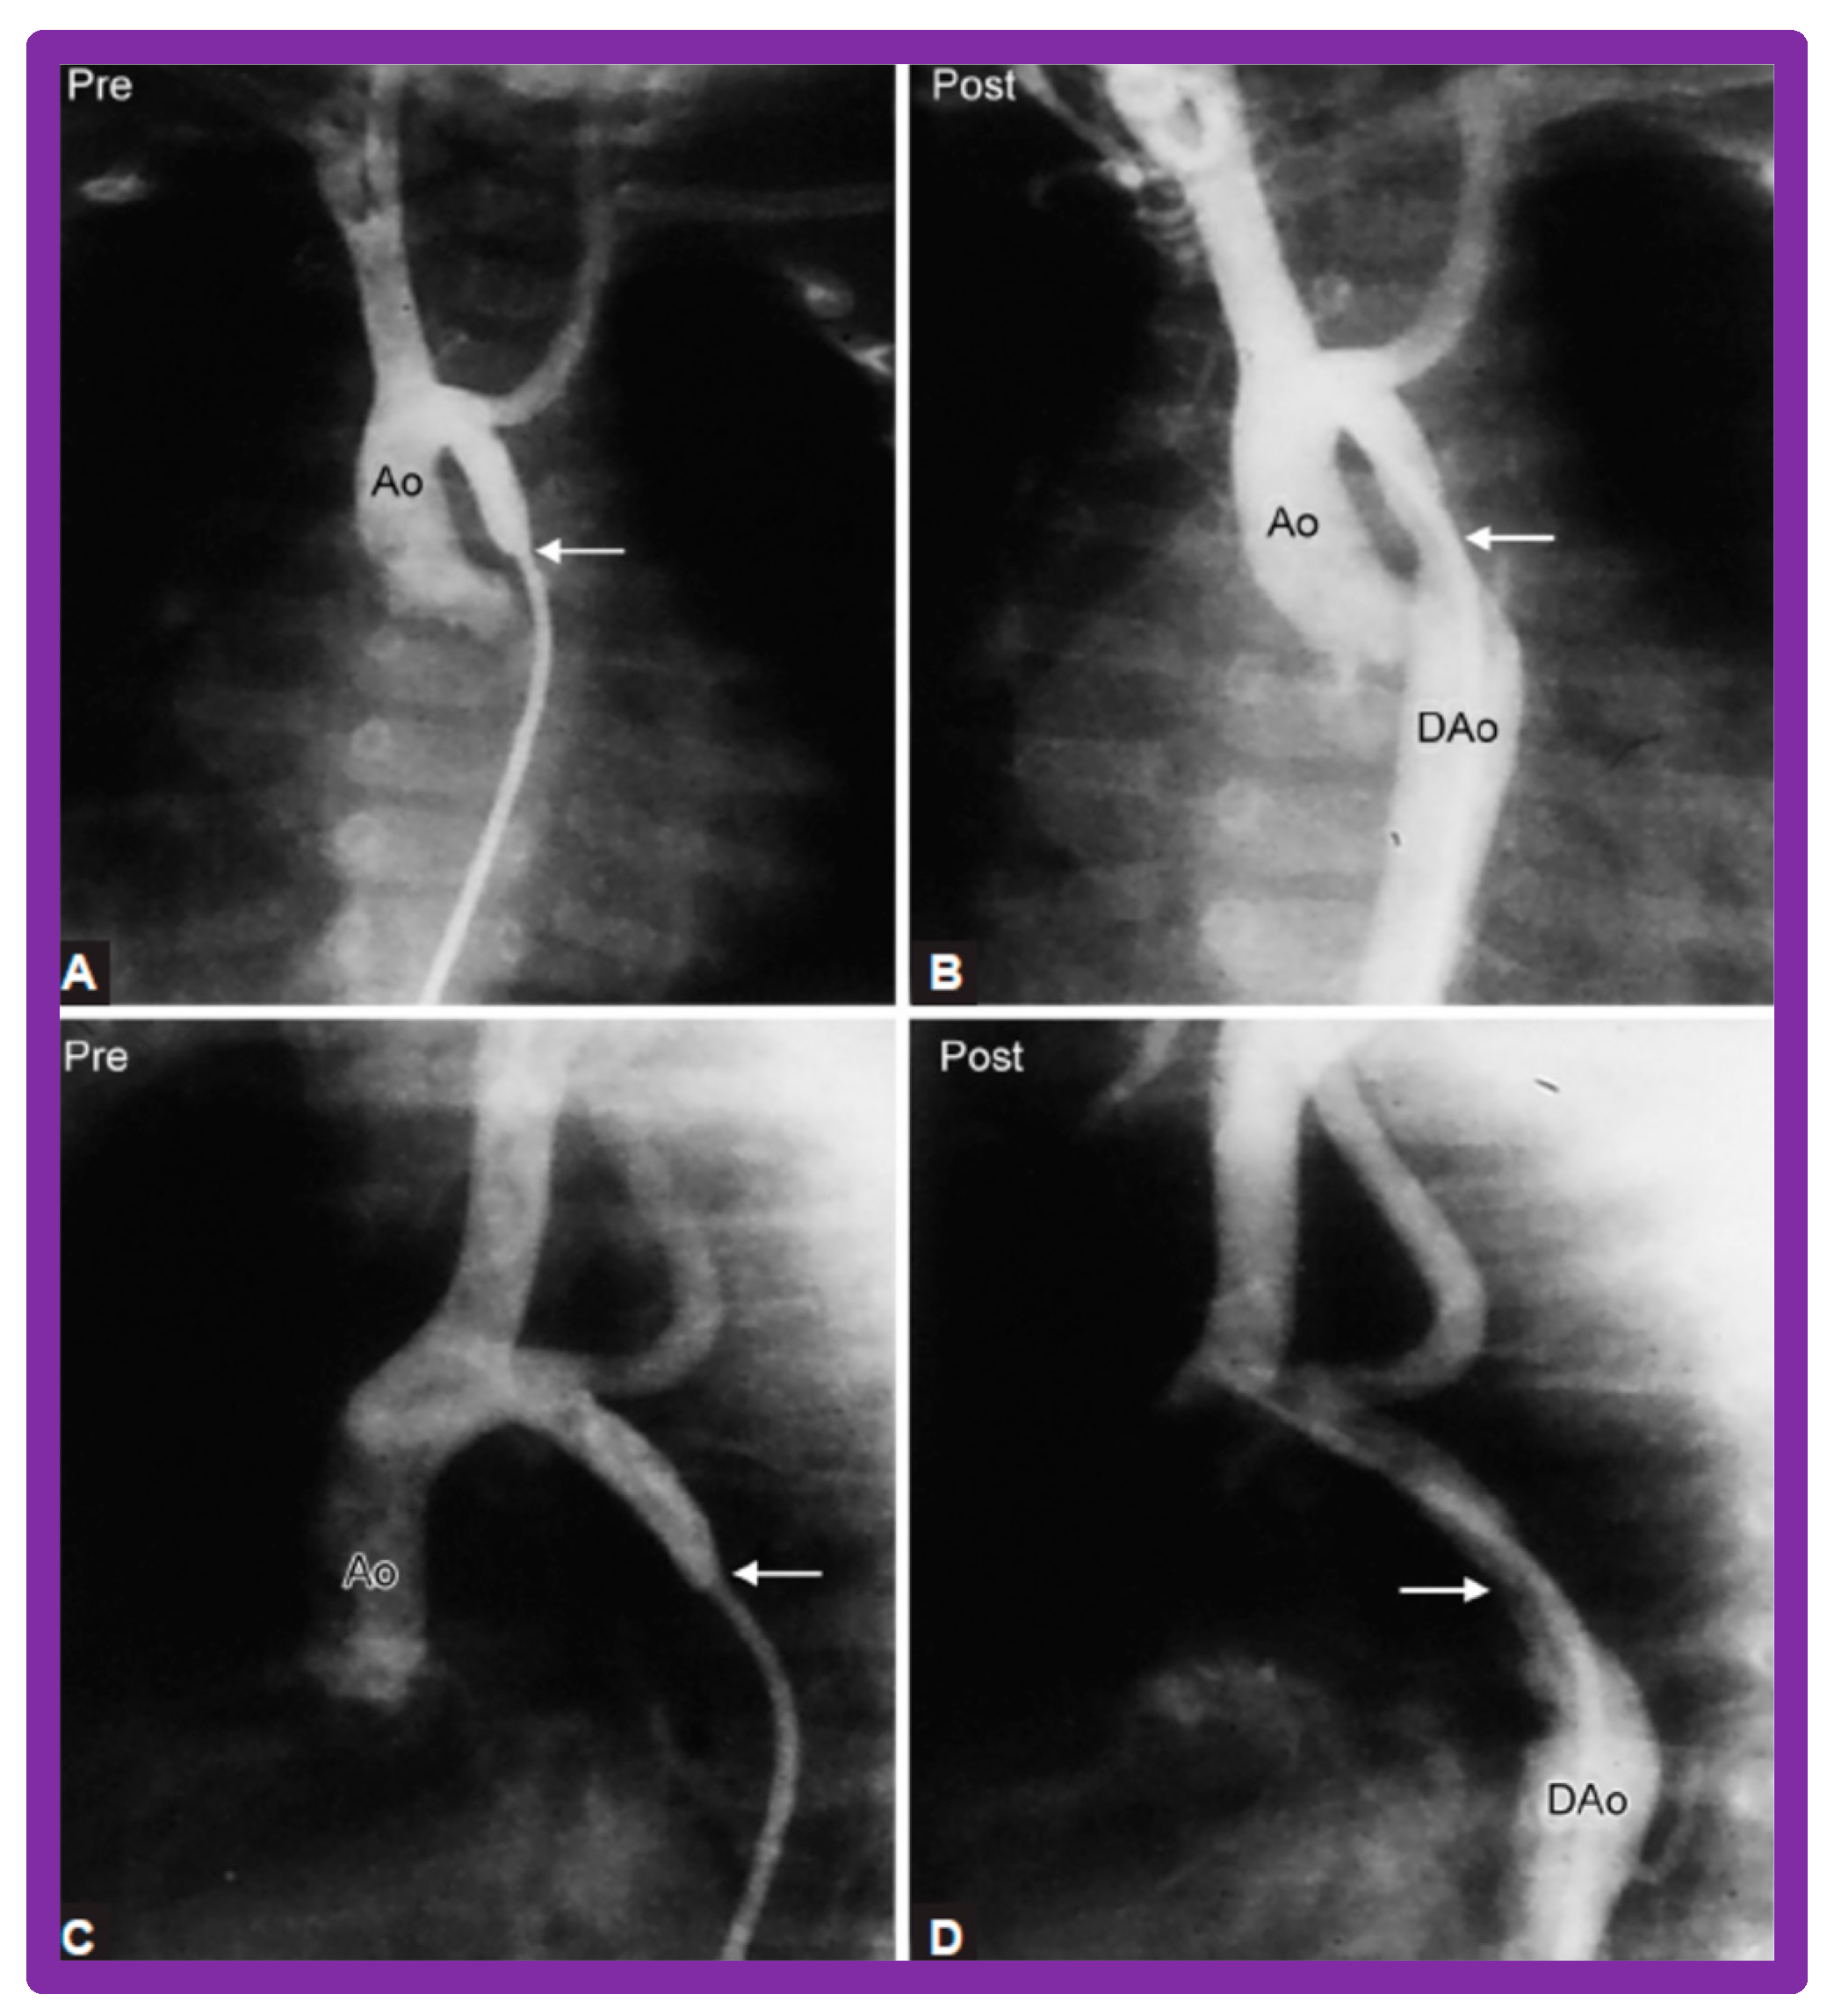

3.3. Aortic Coarctation, Native

4.3. Aortic Coarctation–Native

Revisit BA in the Neonate and Young Infant

4.4. Aortic Coarctation, Postsurgical

5.4. Aortic Coarctation, Postsurgical